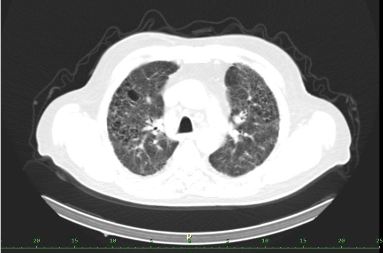

/ Obr. č. 8-10: ldCT plic v rámci vyšetření SPECT/CT. /

SPECT/CT potvrzuje tyto perfuzní defekty. Na ldCT je dále patrná Vámi popisovaná nespecifická intersticiální pneumonie, taktéž emfyzém, to však nevysvětluje diskrepanci mezi perfuzí a ventilací. Jde tedy o tzv. V/P mismatch.